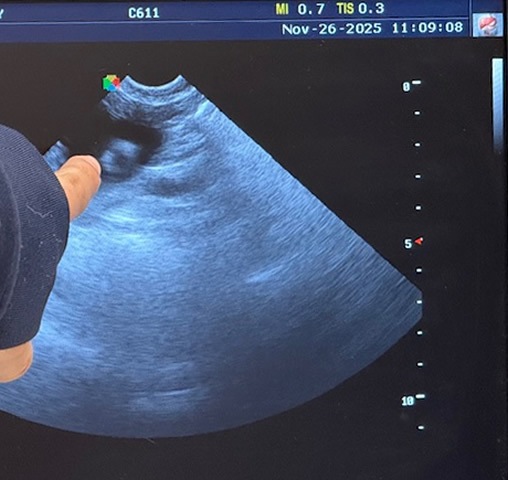

Tasha was very kind to me and decided to have her litter during the DAYTIME, on a WEEKDAY! Seven puppies and we were done! Four boys and three girls; all tri-colored and all huge and thriving. Tasha is tired but as always a great mom and is taking wonderful care of her babies. The ultrasound pic shows one pup and it's beating heart in Nov, and looking at the x-ray, can you make out the babies in her abdomen before they were born? We count skulls and spines - that's how I know how many to expect.